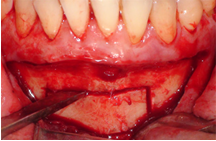

Trong những trường hợp khuyết hỏng xương ổ răng lớn, cần phải ghép xương để cấy ghép implant thì xương khối tự thân là lựa chọn hàng đầu vì có những ưu điểm như tính ổn định cơ học cao chống lại áp lực của mô mềm, ít tiêu,...Vị trí cho xương khối có thể là mào chậu, cằm, xương hàm dưới. Thể tích xương được lấy tùy vào thể tích khuyết hổng cần phục hồi.

LẤY XƯƠNG CẰM GHÉP VÀO VỊ TRÍ KHUYẾT HỔNG

Vị trí khuyết hổng xương ổ răng

Thiếu xương khi ghép implant

Phẫu thuật lấy xương cằm

Ghép xương cằm và xương hạt